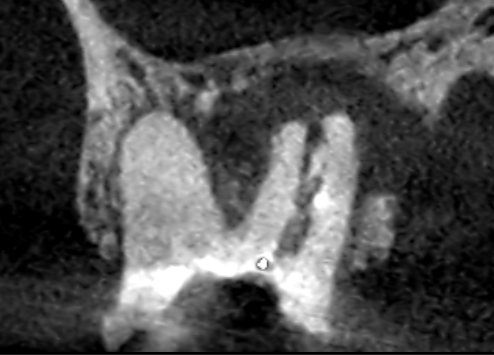

精密再根管治療6ヶ月後の口蓋根の冠状断のCT画像です。舌側の歯槽骨を破って歯肉に到達していた膿の影が消失し、歯槽骨が再生しています(青い矢印)。